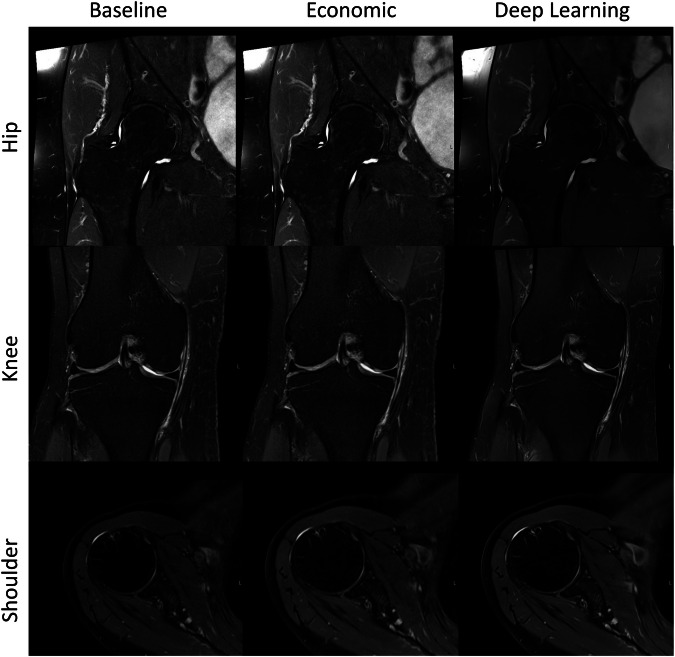

Qualitative image quality

Representative image examples are displayed in Figs. 4 and 5, demonstrating comparable image quality between the accelerated acquisitions (economic, DL) and the conventional clinical baseline, however with reduced acquisition times. No relevant observable image quality differences were reported by the readers (S.A., J.H., S.G., and M.N.).

Fig. 4.

Fig. 5.

Example of the standard hip (top row), knee (middle row), and shoulder (bottom row) T2 TSE for baseline (left column), economic (shortened sequence) (middle column), and DL accelerated (right column) sequences. An acquisition time in hip/knee/shoulder for baseline of 3:21 min/3:08 min/3:01 min, for economic of 2:42 min/2:11 min/2:08 min, and for DL of 1:26 min/0:59 min/1:04 min were achieved